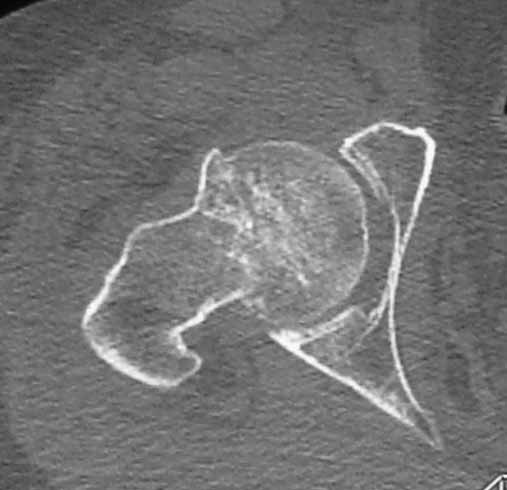

Пациентка 53 лет. ДТП 09.01.12: сочетанная травма: перелом 2-5 ребер справа, ушиб легких; перелом обеих лонных костей без смещения; закрытый перелом проксимального конца правой бедренной кости; открытый оскольчатый внутрисуставной перелом проксимальных концов костей правой голени.

В нашей клинике 11.01 выполнен минимально инвазивный остеосинтез большеберцовой кости (снимки до операции не перефотографировал) с пластикой перемещенными лоскутами дефекта, образовавшегося вследствие некроза кожи на передней поверхности голени. Бедро одномоментно делать не стал, не было уверенности в наличии перелома на уровне шейки. Во время операции смотрел тазобедренный сустав под ЭОПом, головка неподвижна. После операции повторили КТ, стало очевидно, что имеется субкапитальный перелом.

Учитывая тяжесть, возраст больной, а также характер перелома - чрезвертельный оскольчатый осложненный переломом костей таза о остеосинтезе как методе речи быть не может. Вертлужная впадина по КТ выглядит обнадёживающе лишь на первый взгляд - коксартроз и нещадящий остеопороз своё дело сделал. Надо уменьшить шоковый индекс и тяжесть травмы вот в чем дилема, а наносить травму, каковой операция является на раннем этапе несколько опасно. Золотое правило - срочности в ортопедии нет - здесь работает. Сустав однозначно нужно менять, но позже, когда состояние будет абсолютно стабильным, т.к. после травмы появятся подстёгиваемые гиподинамией "подснежники",активно привлекайте смежных специалистов - терапевта, невролога, эндокринолога. Вытяжение за пятку не достаточно, замените, за невозможностью через бугристость болшеберцовой кости, вытяжением через мыщелки бедра (интактным оно уже не является), плюс боковое вытяжение за проксимальную часть бедра посредством тяги за введенный стержень Кюнчера (допустима тяга порядка 6 килограмм!!) Лечение на пол месяца.Далее пациентку, если она не абсолютная бабушка,ждёт этапная операция, если возникнет необходимость, т.к.инвалидизация лучше чем полное обездвиживание. Стержень с блокированием (PFN) средней длины но не короткий (Вы заикнулись о ЭОПе, значит навык есть.). Не торопитесь коллега. Чуть не забыл, тотальное протезирова ние редко используется в сочетании с блокированным остеосинтезом по причине большого дефекта костных структур,выбирать Вам.Вопрос тяжелый и требует более опытного взгляда, чем мой. Как говорится, за спрос не бьют. Извините, что не смог помочь лучше.

Учитывая характер перелома, наличие коксартроза, возможность ранней реабилитации целесообразно расмотреть вопрос о первичном протезировании.( с ревизионной ножкой)

Если позволяет состояние - надо штифтовать, как раз сейчас, есть подходящее "окно". Любым проксимальным гвоздем, можно коротким. Об артропластике думать пока рано, перелом шейки - вколоченный, стабилизируется in situ.

...а перелом еще и роль osteotomia medicata должен сыграть, то есть на несколько лет снизить выраженность болезненных проявлений артроза.